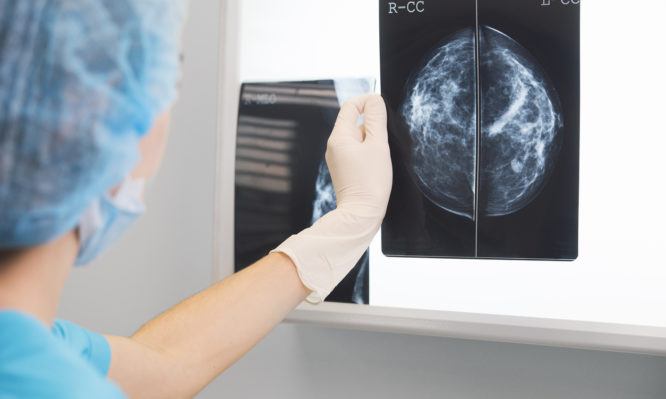

Από την μαστεκτομή έως την εποχή της ελάχιστης χειρουργικής παρέμβασης

Ο μαστός για την γυναίκα από την αρχαιότητα μέχρι και τη σύγχρονη εποχή αποτελούσε και αποτελεί το κύριο όργανο έκφρασης της θηλυκότητάς της. Η διενέργεια μιας ακρωτηριαστικής επέμβασης, όπως είναι η μαστεκτομή, καθώς και οι αλλοιώσεις του δέρματος που προκαλούνται από πιθανή μετεγχειρητική ακτινοθεραπεία, μπορεί να της προκαλέσουν σοβαρά ψυχολογικά αλλά και πρακτικά προβλήματα.